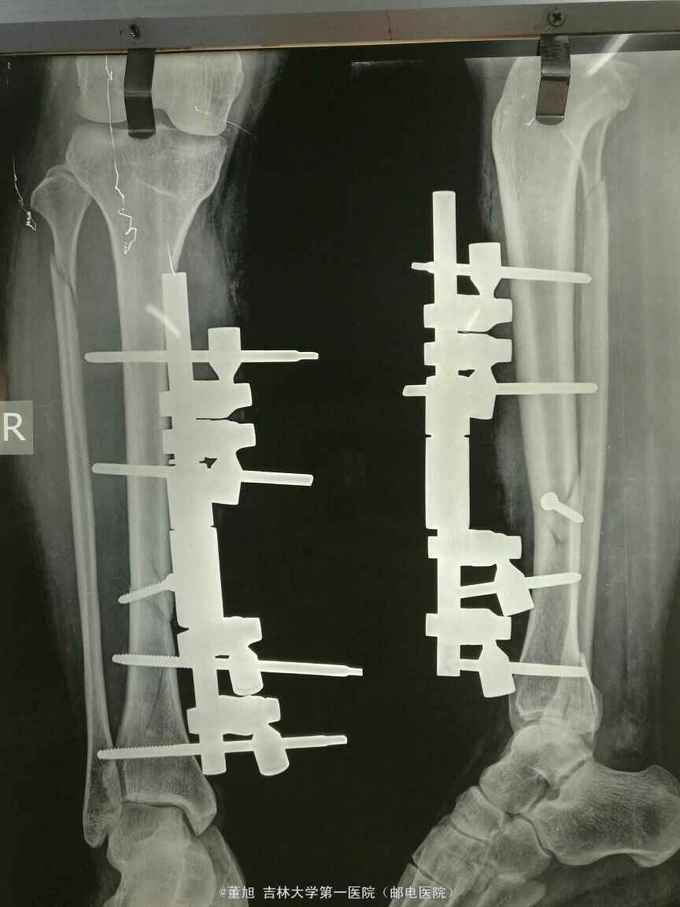

诊断:右胫骨骨折 治疗:骨折切开复位外固定架固定术

胫骨中段骨折的内固定方式